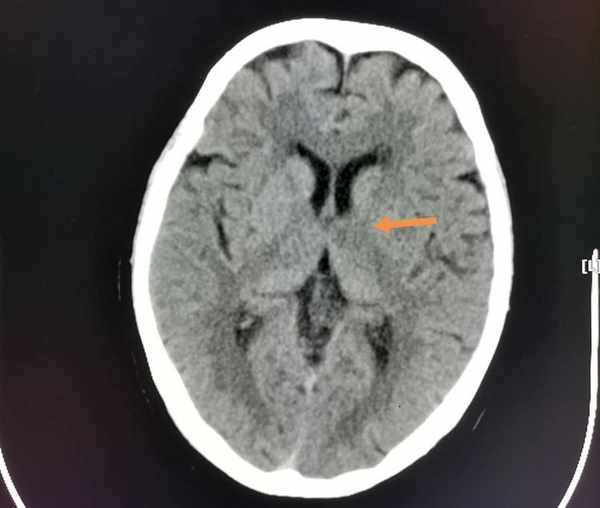

像這位69歲老太太,頭疼、右側肢體發麻無力,急診CT排除了腦出血,同時發現左側丘腦和內囊密度略减低,提示腦梗死。

5天后複查,更典型了:

這種小範圍腦梗死(腔隙性腦梗死),治療效果一般都很好。